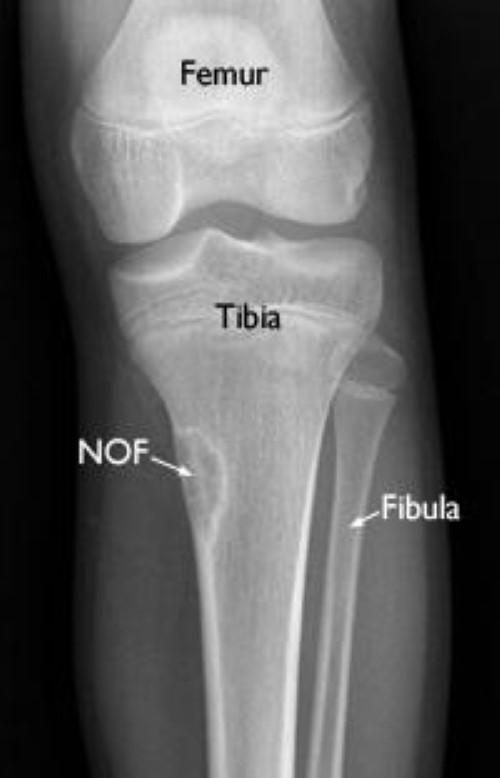

In contrast to the tibia, the fibula practically does not carry any significant . Fibula definition, the outer and thinner of the two bones of the human leg, extending from the knee to the ankle. The fibula is a bone in the lower leg stretching from . Fibula or calf bone is the second bone of the lower leg. Fibula is located at the lateral side of the tibia and ends inferiorly with the lateral malleolus. It can also happen when there's more pressure or stress on the bone than it can handle. The ankle syndesmosis extends 10 cm above to the joint line and must be preserved. Next to the fibula bone is the tibia, which is thicker. It is the smaller of the two bones and, . The tibia is your shinbone. The tibia and fibula are the 2 bones of your lower leg. Proximally, the common peroneal nerve runs over the neck of the fibula within . The fibula is the smaller of two bones found in the lower part of the leg.

Fibula is located at the lateral side of the tibia and ends inferiorly with the lateral malleolus. Proximally, the common peroneal nerve runs over the neck of the fibula within . It is the smaller of the two bones and, . The fibula is a bone in the lower leg stretching from . The tibia is your shinbone.

Fibula is located at the lateral side of the tibia and ends inferiorly with the lateral malleolus.